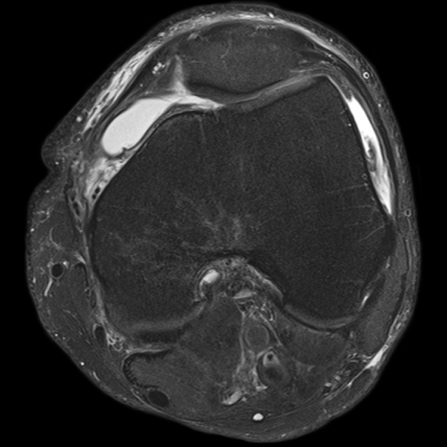

Khớp gối: Nhiều chuỗi xung 3D cho độ phân giải rất cao, hiển thị sụn viền rõ cùng nhiều chương trình giúp đánh giá thoái khớp khớp sớm

Hình 16. Hình ảnh MRI khớp gối